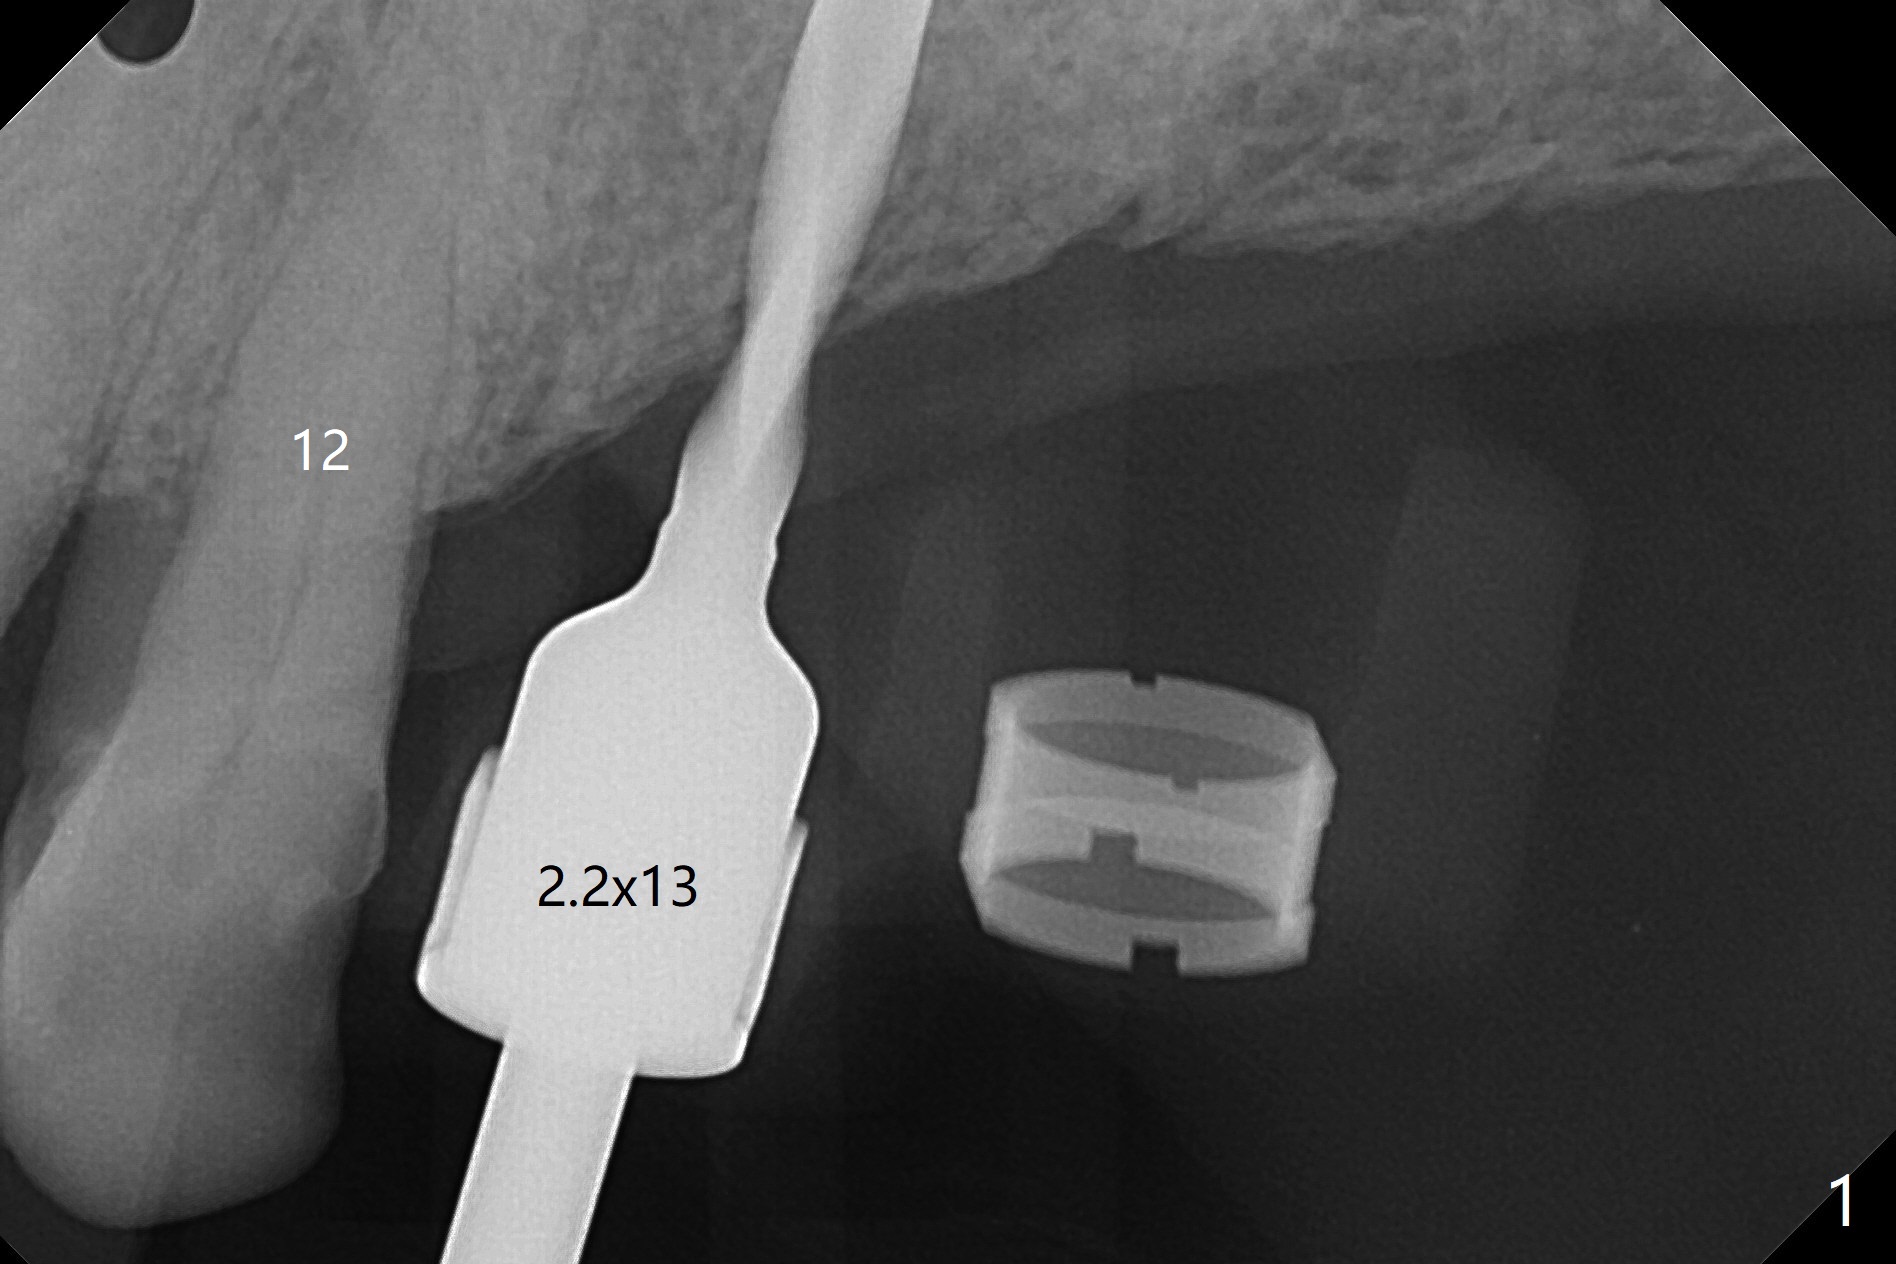

PA is taken after 2.2 mm drill reaches the depth at #13 to confirm that the osteotomy is parallel to the long axis of the tooth #12 (Fig.1). Fixture mount is used to place a 4x10 mm implant at #13 and stays as an anchor pin while osteotomy and sinus lift are being conducted at #14 (Fig.2). In fact there is discrepancy in depth using the guide. For example the last drill for osteotomy is 4.5x7.3 mm according to design, whereas 4.5x11.5 mm drill has to be used before the sinus floor has small area of perforation without sinus membrane breakage. Autogenous bone harvested from the osteotomy, PRF membrane and a 4.5x10 mm dummy implant are used for sinus lift (Fig.2). The placement depth of the implant at #13 has to be adjusted multiple times until satisfaction (Fig.2-5). The implant at #14 is infected and loosened 1.5 months postop; after its removal, the sinus floor is absent without membrane perforation; the large defect with basically intact buccal and palatal walls is grafted (Fig.6 *). Four to five months later, use the same guide and drill sequence until 3.5x7.3 mm drill. Insert a 4x10 mm dummy implant to the 2nd line of 12 mm offset and take 5x5 cm CT to determine the diameter and depth of a final implant. Use healing screw. The pattern of bone graft changes 3 months postop (Fig.7, as compared to Fig.6). Return to Upper Arch Immediate Implant, Trajectory II 矫正,糖尿病,种植水平 Xin Wei, DDS, PhD, MS 1st edition 08/06/2019, last revision 12/06/2020